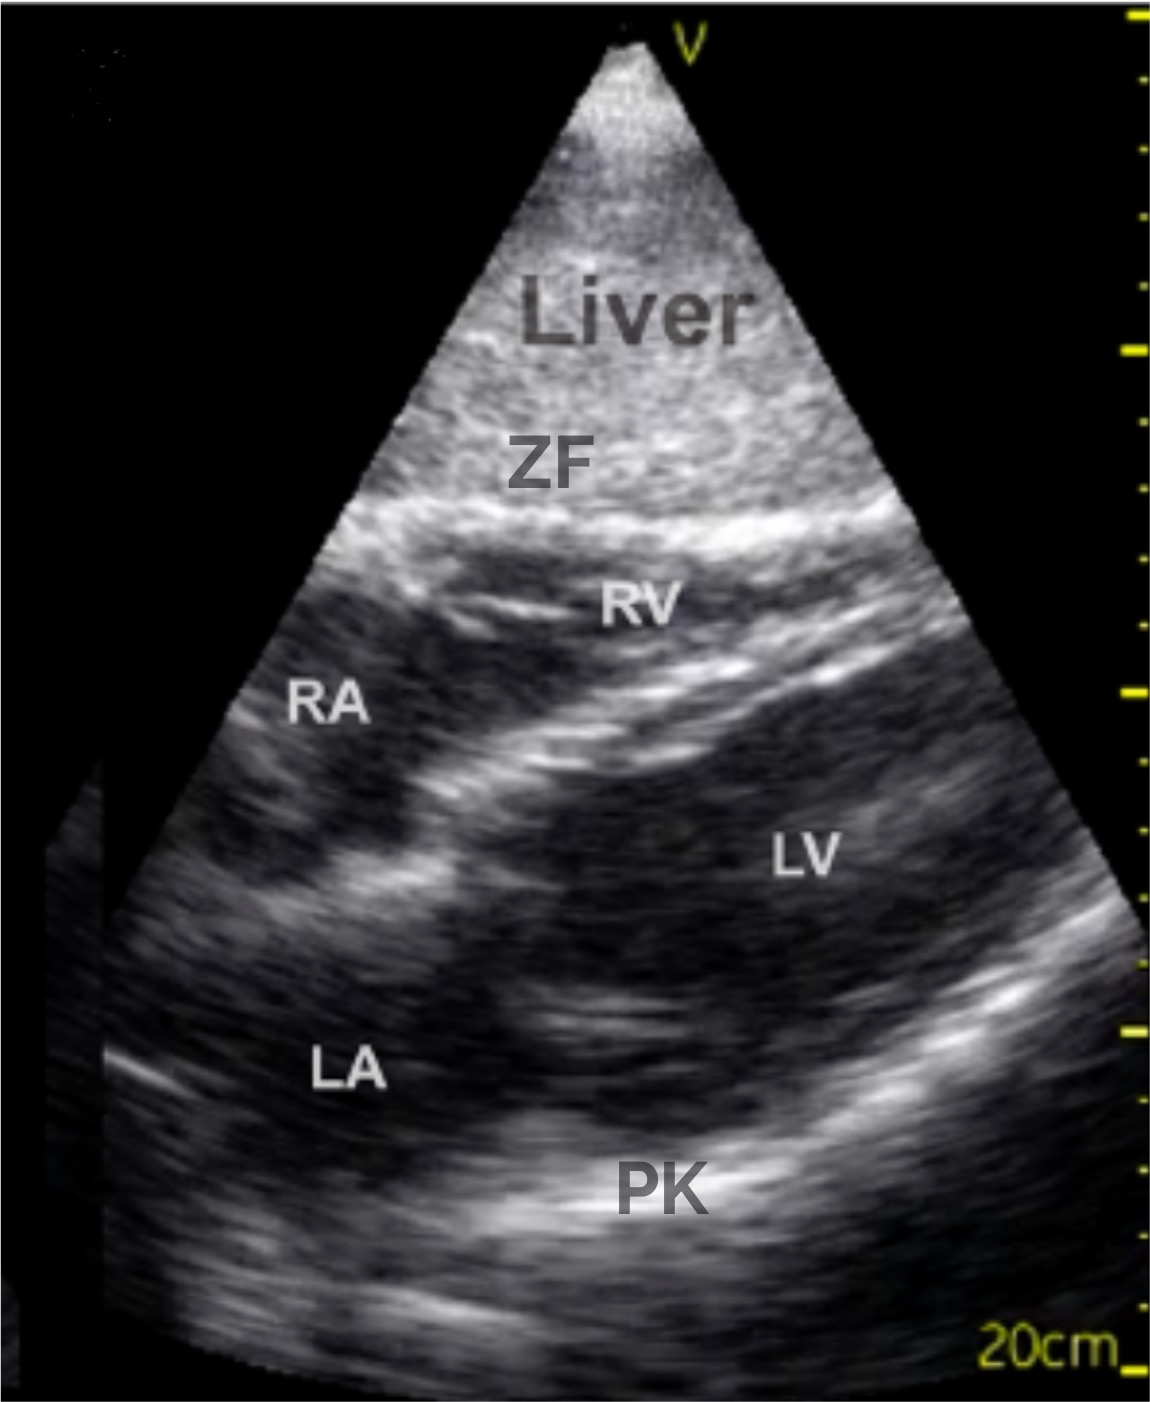

Zunächst sichere Orientierung

- Leber

im Vordergrund (Liver ➜) - Dahinter Zwerchfell

(ZF ➜) - Direkt darüber das Herz, meist beginnend mit dem rechten Atrium (RA ➜) und rechten Ventrikel (RV ➜) und folgend mit dem linken Atrium

(LA ➜) und linken Ventrikel (LV ➜) - Perikard

als echoreiche Linie, die das Herz umgibt (PK➜)

Im subxiphoidalen Schnitt zeigt sich das Herz vollständig in der Vierkammeransicht hinter der echoreichen Linie des Zwerchfells

Im Vordergrund liegt das homogene Parenchym der Leber